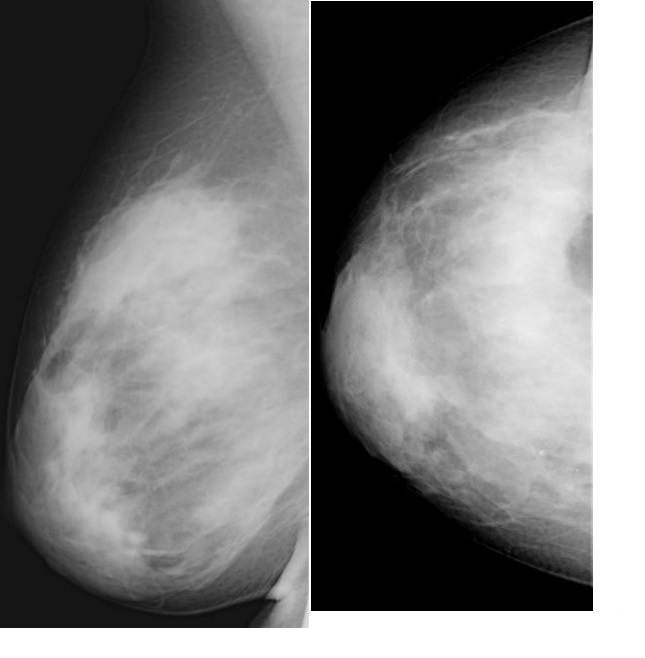

Основным показанием к проведению данного хирургического вмешательства является выраженное опущение (птоз) молочных желез – состояние, при котором соски находятся аномально низко. Степень мастоптоза принято оценивать по положению соска по отношению к складке под грудью (субмаммарной складке).

Существует 3 степени птоза молочных желез:

1 степень характеризуется слабым опущением железы, сосок располагается на линии субмаммарной складки;

2 степень – сосок находится под складкой, но выше большей части тканей железы;

3 степень – сосок на уровне нижнего полюса железы и смотрит вниз.

Псевдоптоз молочных желез – сосок находится над складкой, хотя сама молочная железа опущена.